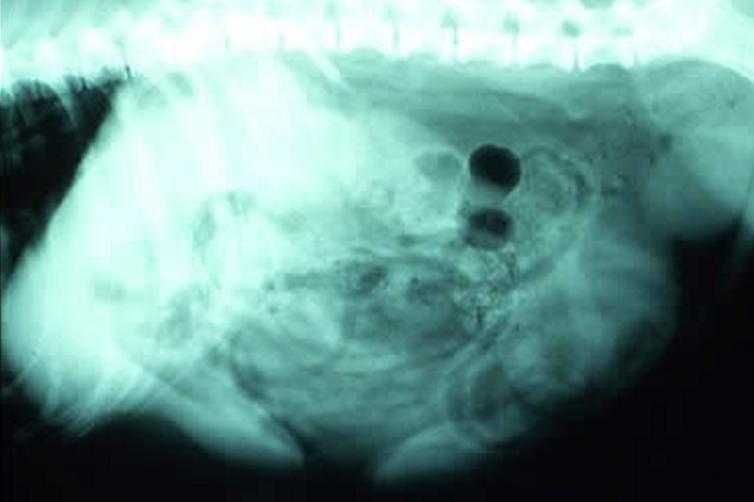

X光线检查:腹部侧位片为主,重点观察骨骼是否完整,骨密度发育如何,是否存在明显泌尿系统结石,可见腹腔整体对比度,肝脾肾位置、轮廓、大小。

前列腺增生X光线图